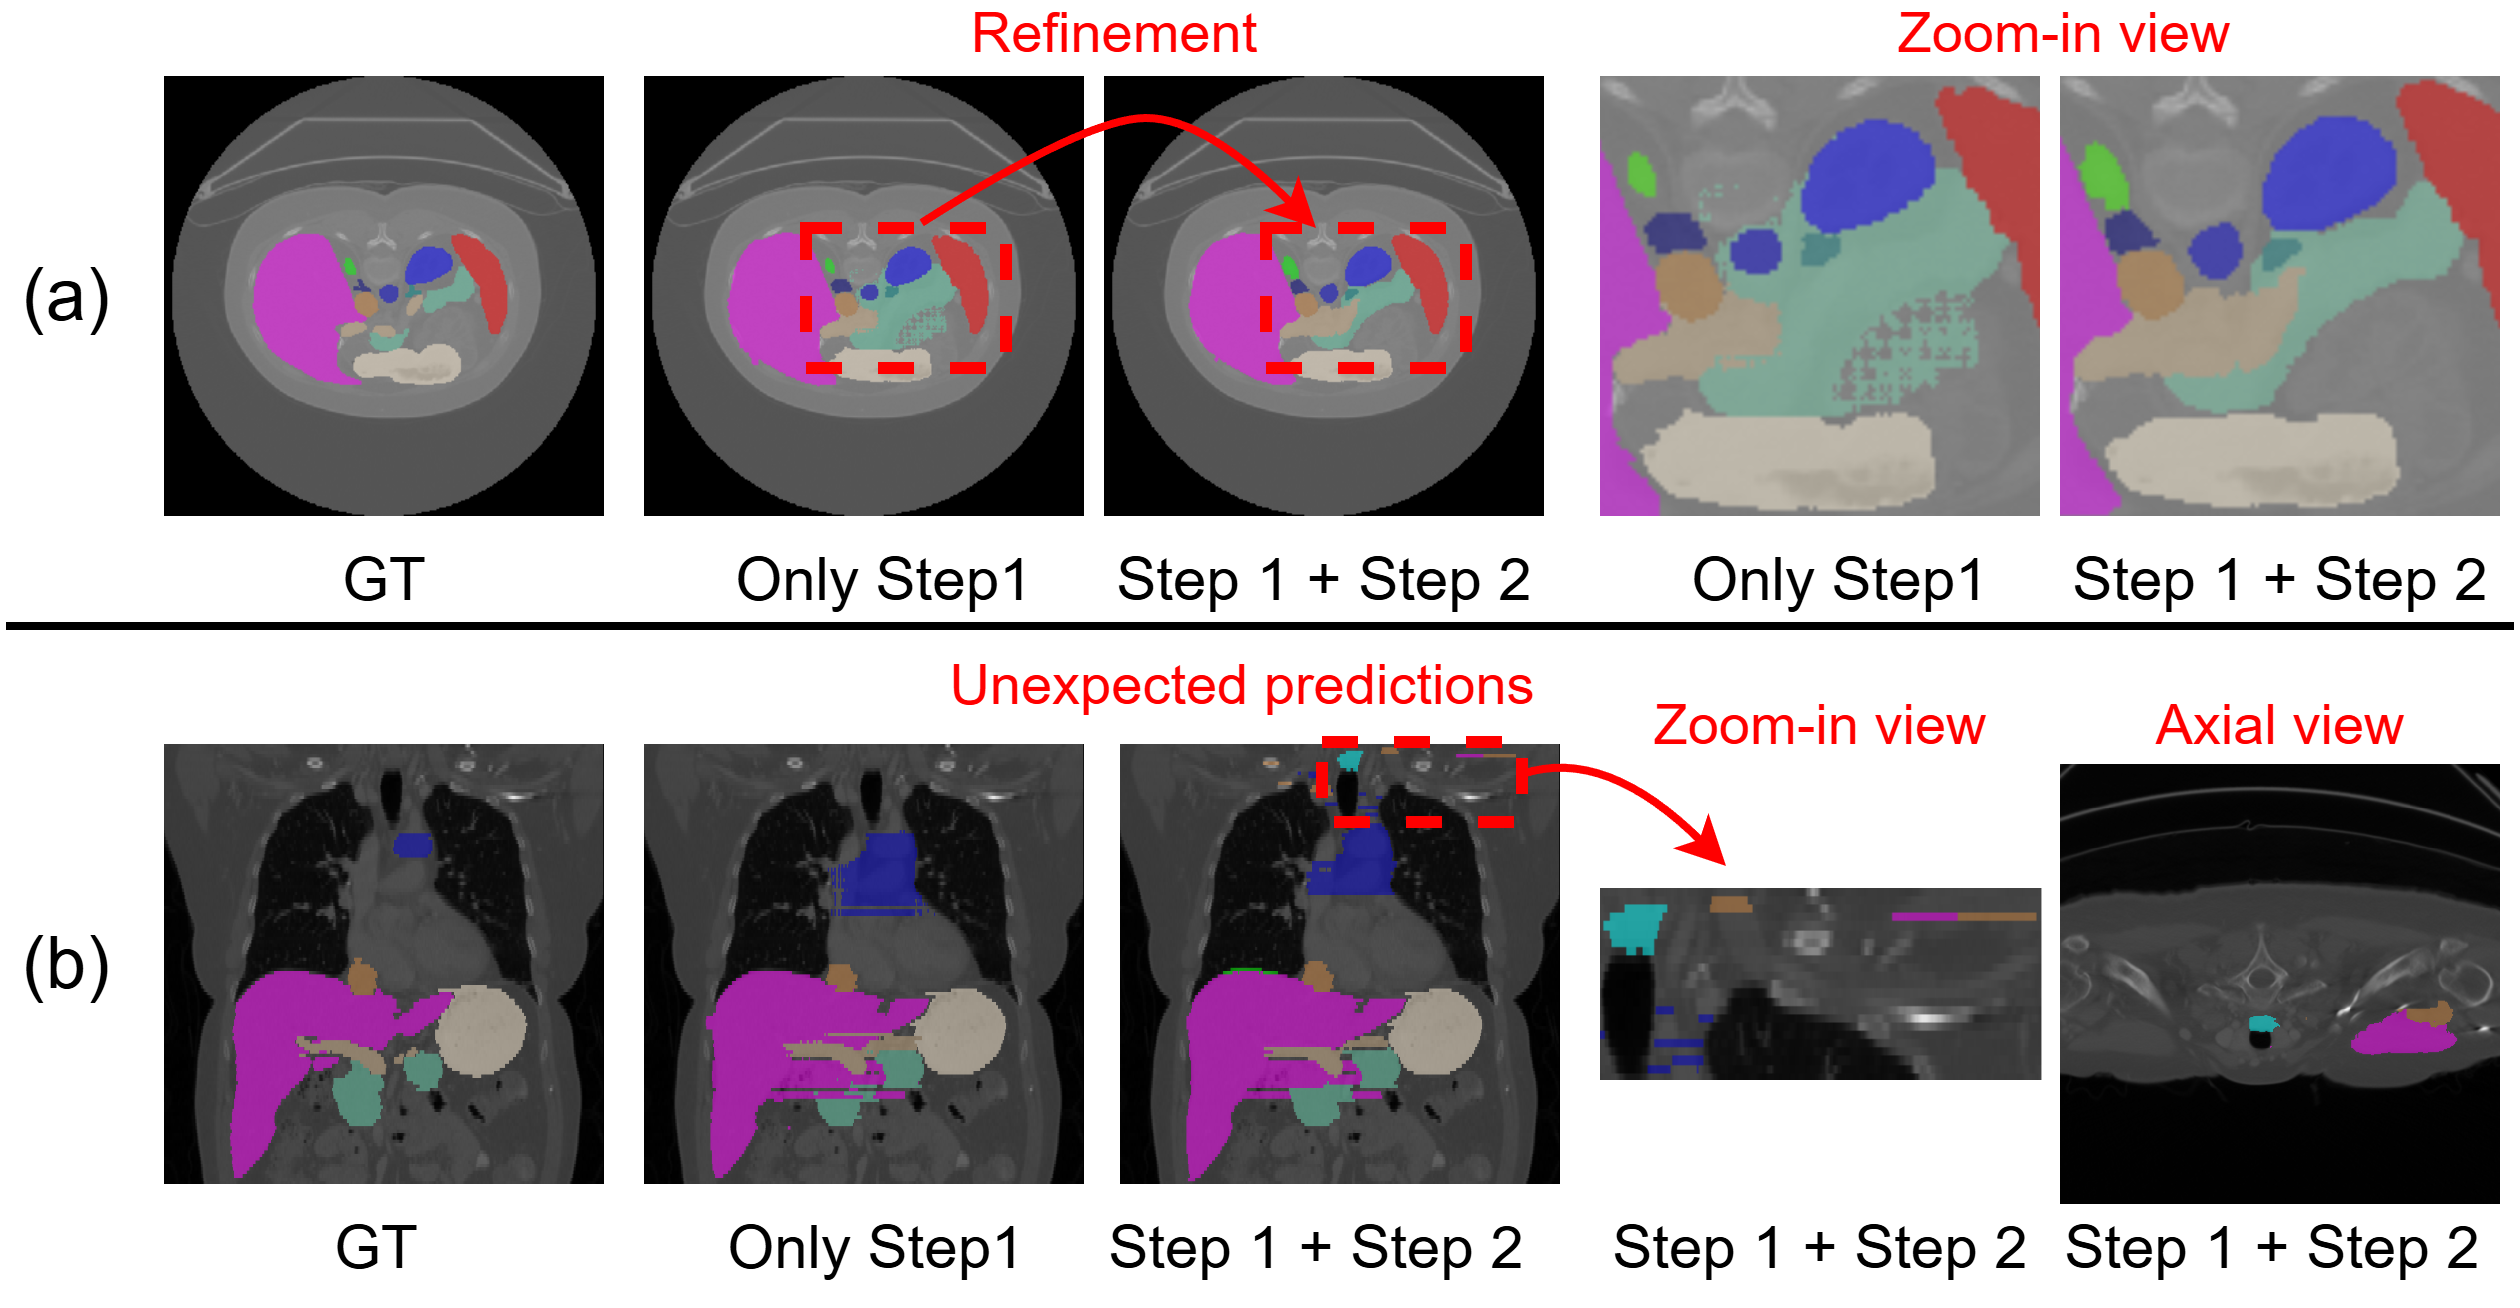

Refer to caption

Figure 5: Comparisons with different output predictions for Step 0, Step 1, and Step 2.

Refinements. Table 5 presents experimental results for output predictions at different steps on the BTCV and AMOS datasets. The results show a gradual improvement in performance, starting from the initial prediction at Step 0 (UNet), followed by the second prediction after the first refinement at Step 1 (SAM 2), and finally the third prediction after the second refinement at Step 2 (SAM 2). Figure 5 visualizes these comparisons across the three different steps. The results clearly demonstrate how the hole is progressively filled through the two refinements, highlighting the effectiveness of our model’s refinement process.

Figure 6: Benefits for refinement by Step 2.

Although the results decreased slightly from 82.77% to 81.17% Dice, we find a potential refinement benefit illustrated in Figure 6(a). Through Step 2, the green area is refined and becomes more accurate, demonstrating the significant potential of the refinement process. As a result, we plan to incorporate this approach into our method. However, the refinement introduced by Step 2 also has some drawbacks. In Figure 6(b), we show orthogonal planes in relation to the axial plane (a sequence of the axial plane images is fed to SAM 2). The top portion of Figure 6(b) presents unexpected predictions. Since SAM 2 assigns a temporal position of 0 to the prompted frames, which are always involved in memory attention, the incorrect relative temporal positioning leads to these unexpected and incorrect predictions. We will address this issue in the next section.